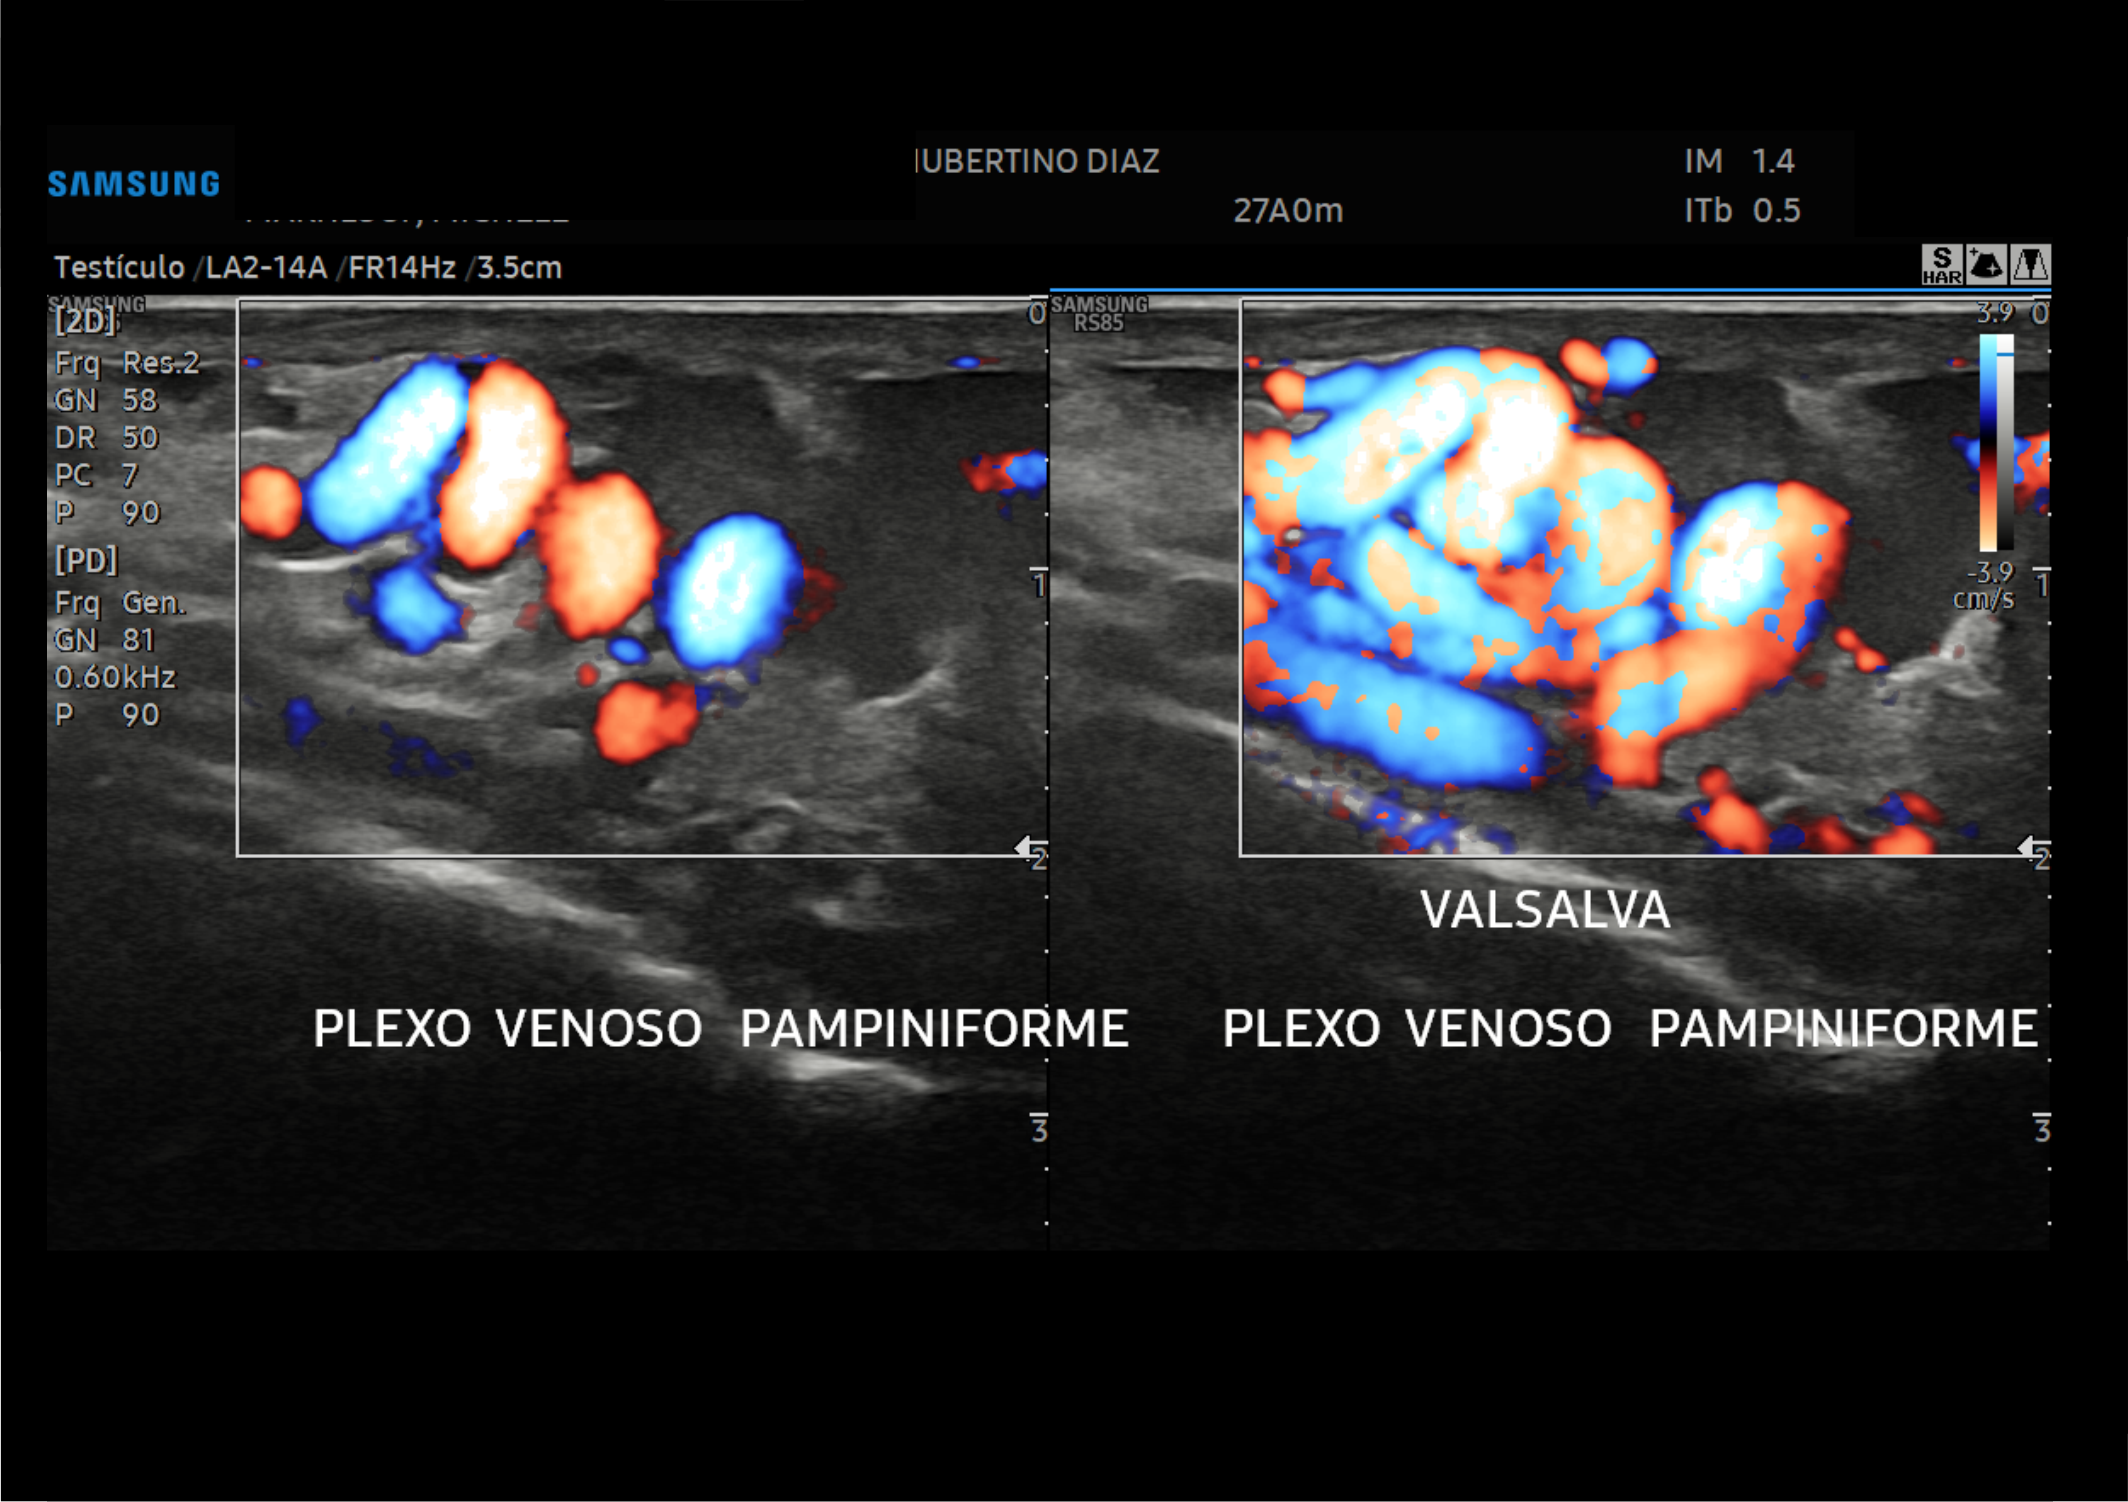

En Diagnoimagen incorporamos un enfoque de ecografía multiparamétrica, combinando modo B, Doppler color, Doppler de microflujo y elastografía, lo que nos permite una evaluación más completa y precisa en múltiples patologías.

🔹La ecografía Doppler permite evaluar el flujo sanguíneo en arterias y venas, siendo fundamental para el diagnóstico de insuficiencia venosa, várices, trombosis, estenosis carotídea y patología hepática.